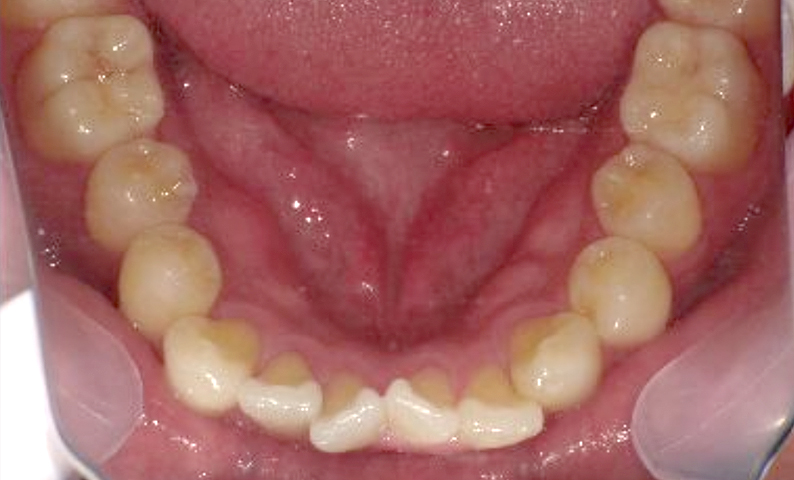

症例_025 上下顎の部分矯正

治療期間:13ヶ月金額:51万円+税女性前歯のガタガタ出っ歯

| Before | After |

|---|---|